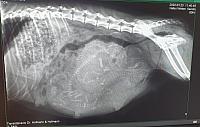

Am 27. März 2020 hat unsere "Josilie" den Welpen ihres zweiten Wurfes das Leben geschenkt und hat es sehr spannend gemacht. Wir dürfen uns über zwei tricolour-Hündinnen, zwei black & tan-Rüden und eine black & tan-Hündin freuen. Mama "Josilie" und ihre Fell-Babys haben die Geburt gut überstanden, die Welpen entwickeln sich prächtig und haben schon schön zugenommen.